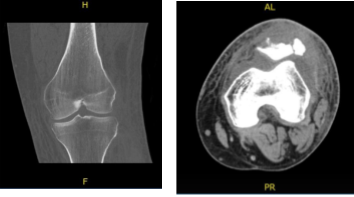

A result for MRI was presented and shown mildly displaced patellar fracture with accompanying longitudinal tear of the distal quadriceps tendon. Bone contusion of the lateral femoral condyle. Large left knee joint effusion. Minimal undersurface fraying along the course of the medial meniscal posterior horn.

MRI – 3T Left Knee Non Contrast

A result for CT SCAN on Left knee was presented and shown comminuted displaced fracture of the patella with new fractures not seen on previous examination status post-surgery. Thickened appearance of the quadriceps tendon, there is excluded.

CT – Left Knee Contrast